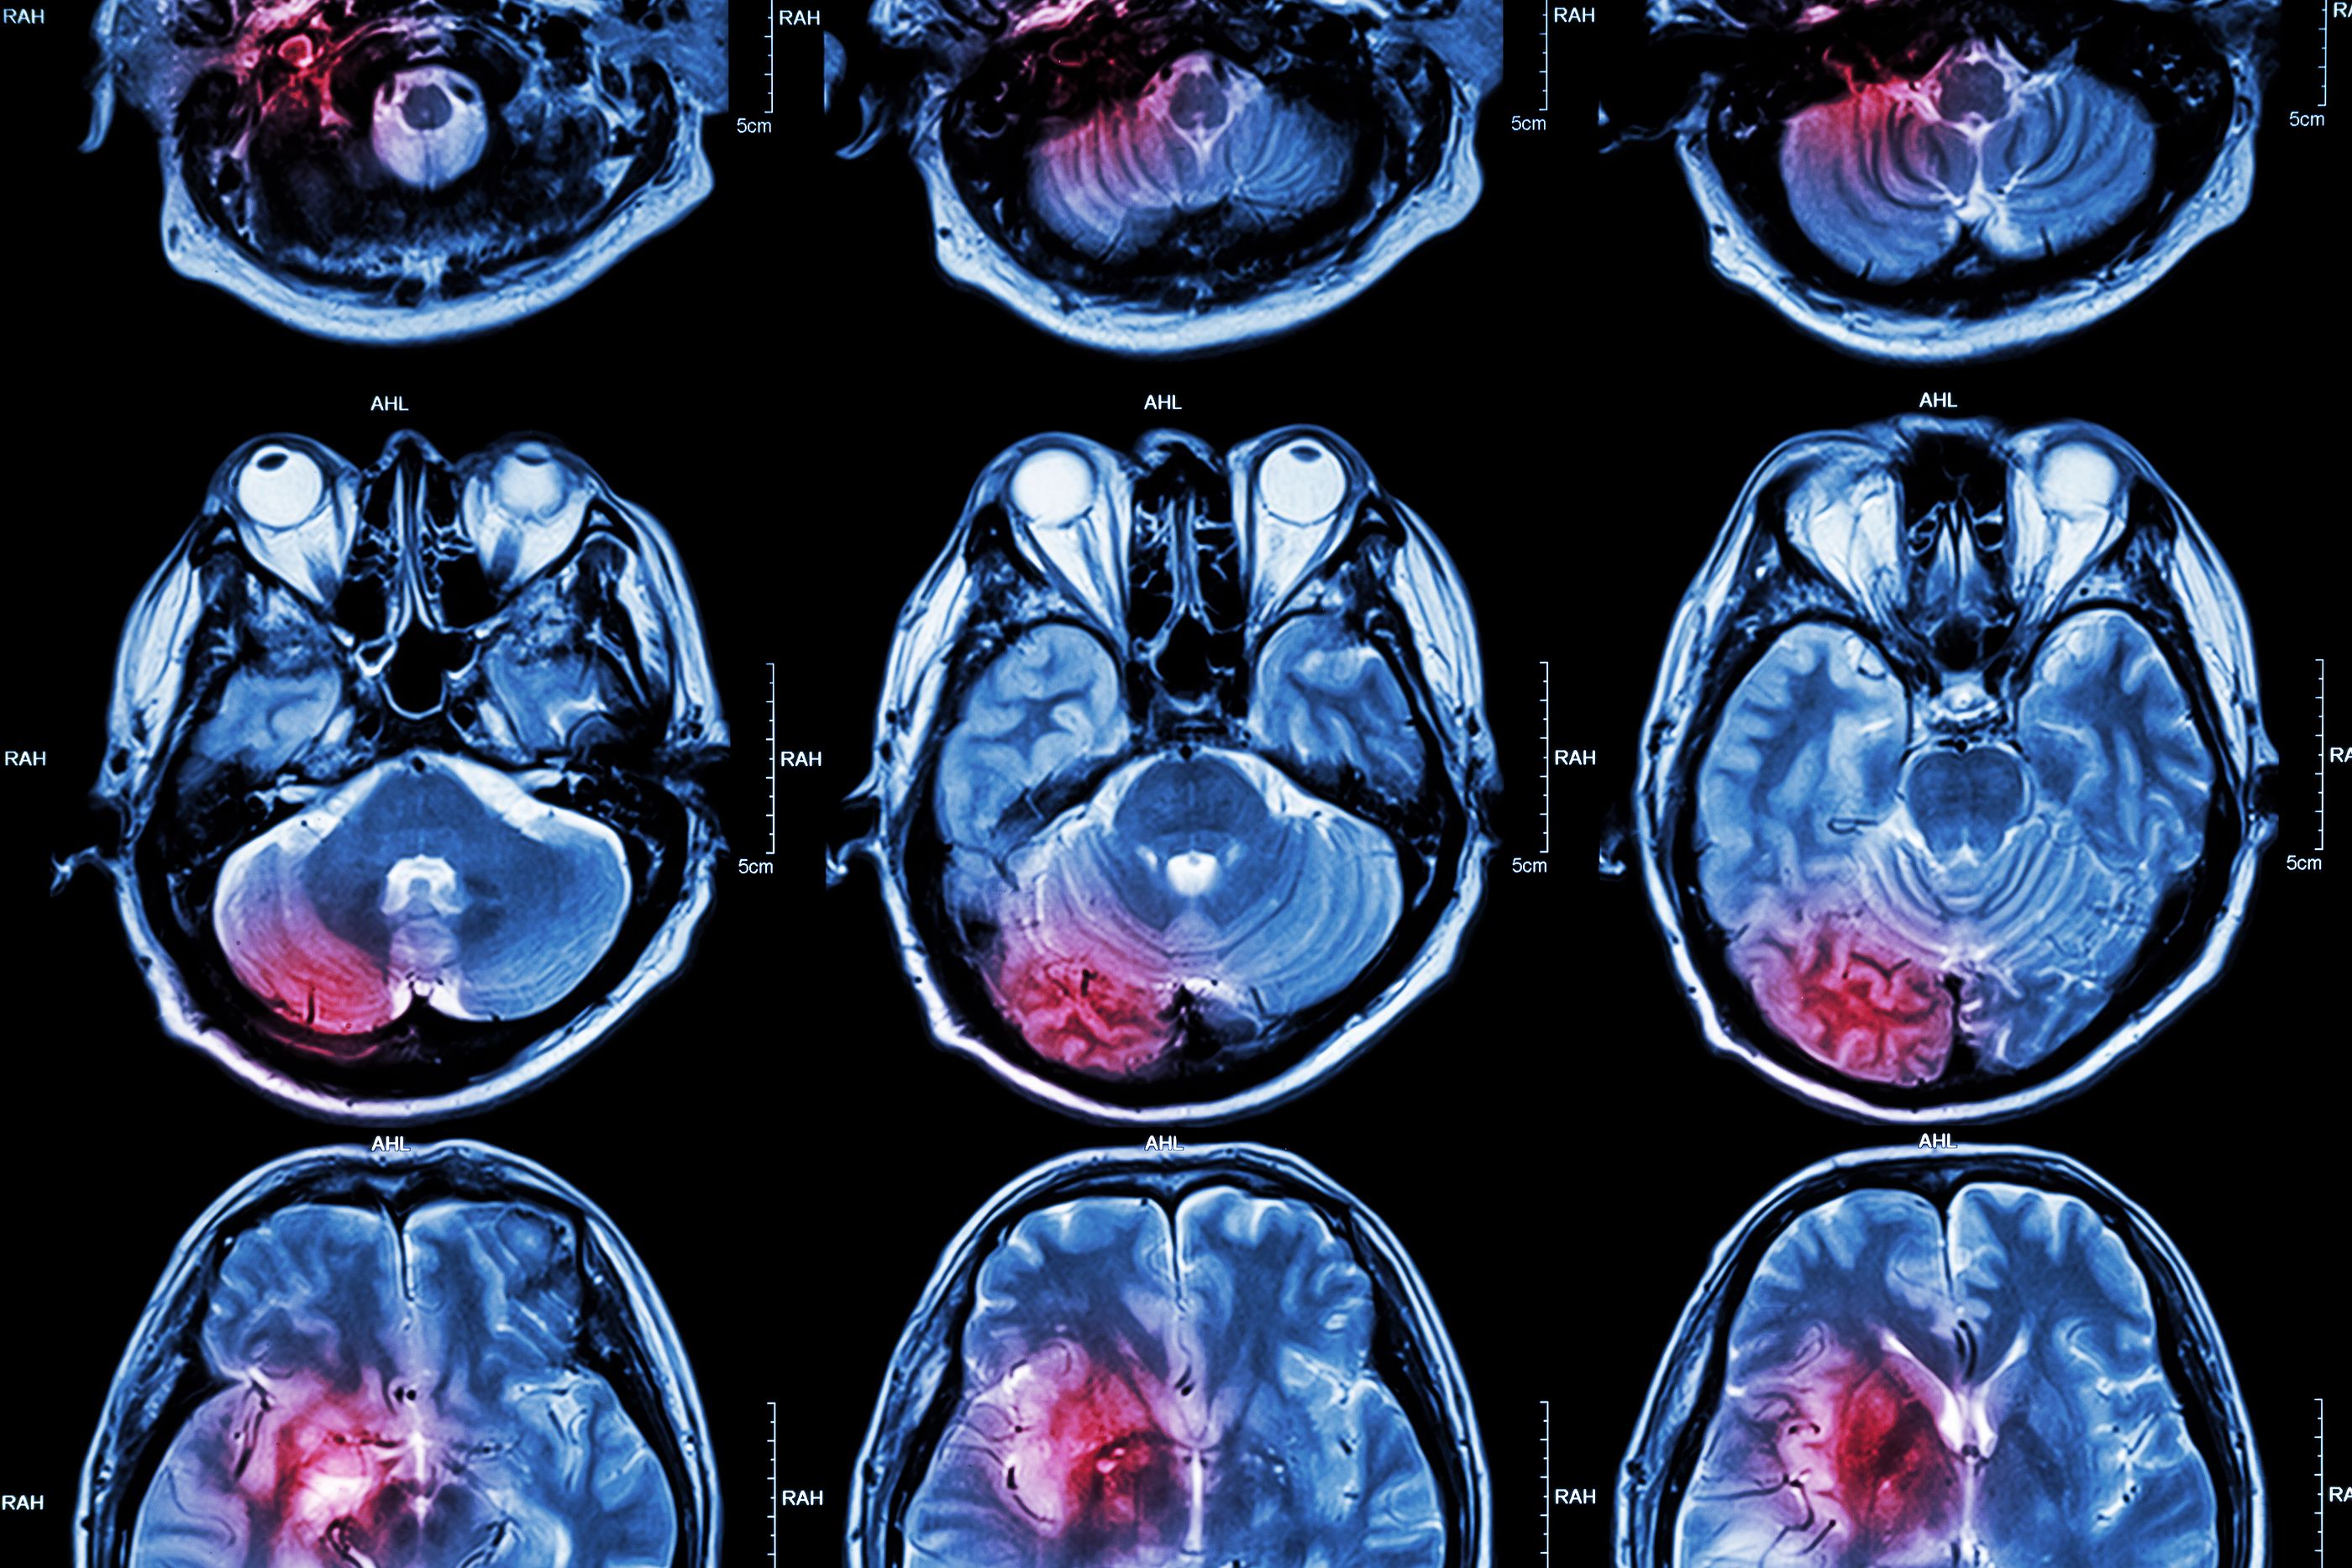

El tratamiento hizo desaparecer el tumor de su garganta y de la metástasis en sus pulmones se encargaron la quimioterapia y la cirugía. Pero su caso no es el único beneficiado por esta terapia, la extensión de vida media de los pacientes con cánceres cerebrales recidivantes o metástasis que la reciban es de 17,6 meses, apuntan los autores del estudio.

El tratamiento, que se está mostrando incluso más eficaz que la quimioterapia en enfermos con tumores en cabeza y cuello combina dos fármacos que logran reforzar el sistema inmunitario, el nivolumab y el ipilimumab.